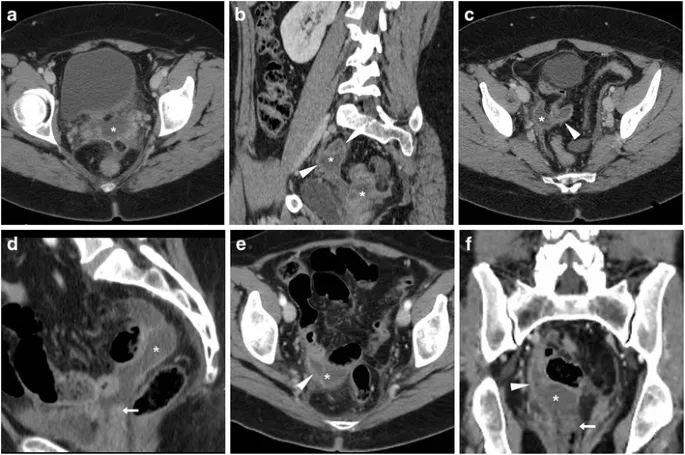

- Hemorrhage: Assess vitals, CBC. Pelvic US for hematoma; CT-A for active extravasation.

- Ureter: ↑Cr, flank pain. Dx: CT urogram, retrograde pyelogram.

- Bladder: Gross hematuria. Dx: Retrograde cystogram.

⭐ Ureteral injury often presents subtly 5-10 days post-op with flank pain, fever, or watery vaginal discharge (urinoma), not immediate anuria.